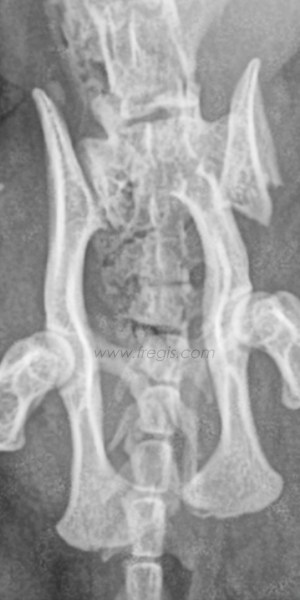

Anatomie du bassin osseux chez le chien

Fracture du bassin chez le chat